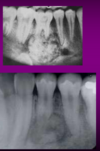

– Osteoma periosteal ou periférico ou exofítico: massa polipóide ou séssil na superfície do osso.

– Osteoma endosteal ou central: no osso medular.

Crescem lentamente na superfície da mandíbula ou da maxila como pólipos ou massas sésseis na superfície do osso.

Podem alcançar grandes proporções,

resultando em deformidade facial.